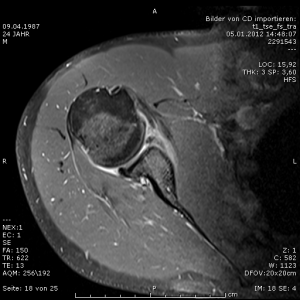

Zu kleine Schultergelenkspfanne im MRT.

Bei der Schultergelenksluxation (Ausrenkung) rutscht der Oberarmkopf aus der Schultergelenkpfanne, was in der Regel mit dem Abriss der vorderen Gelenklippe (sog. Labrum) verbunden ist. Gelegentlich kommt es auch zum Abriss von knöchernen Fragmenten der Pfanne. Eine Erstluxation ist häufig die Folge eines Sturzereignisses, danach neigt die vorgeschädigte Schulter insbesondere bei Jugendlichen und jungen Erwachsenen zur Spontanluxation bei alltäglichen Bewegungen. Gelegentlich ist anlagebedingt eine Laxizität der Schulterbänder vorhanden, so dass Verrenkungen der Schulter nach vorn und/oder hinten möglich sind. Bei machen Patienten ist die normalerweise birnenförmige Schulterpfanne nicht korrekt entwickelt, sodass der große Oberarmkopf kein suffizientes Widerlager hat und zur Luxation ohne Unfallereignis neigt.